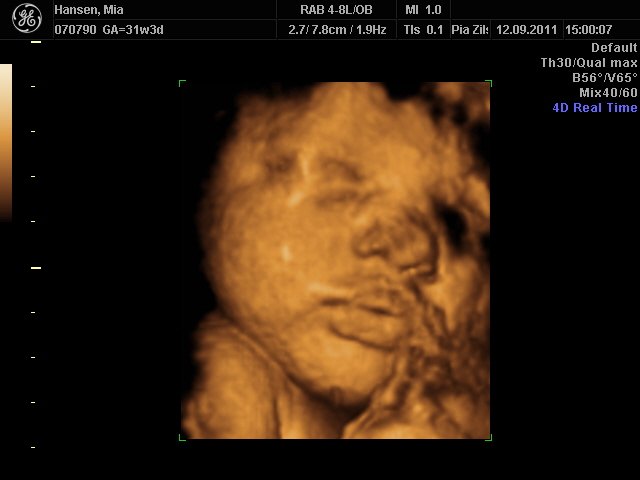

Så er vi næsten lige kommet hjem fra scanningen i københavn

Hold da helt op hvor hun kunne charme sin mor & far, hun er bare så lækker, hun lå lige som hun skulle for at få gode billeder af hende

Hun er stadigvæk en rigtig putterøv, men vi fik en masse smil og trut-munde af hende

hun har lange øjenvipper og hår i nakken

Mia 31+3